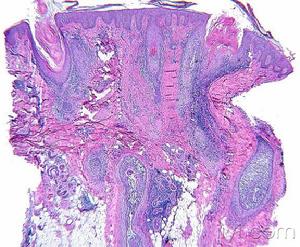

可分為三期,即紅斑期、斑塊期和腫瘤期,但三期皮損可部分重疊,因而臨床上可同時見到三期皮損。

蕈樣黴菌病(一)紅斑期皮損多呈單個或多個扁平萎縮性斑片,表面被覆有鱗片,大小不一,通常界限清楚,顏色自橘紅至暗紫紅色不等。常見於被覆部位;自覺劇癢或無明顯自覺症狀,偶見皮損消退而不留瘢痕。臨床上類似銀屑病、濕疹、慢性接觸性皮炎、異位性皮炎、神經性皮炎等而較易誤診,因此對套用通常治療方法而難以醫治的此類疾病,應每3個月活檢一次,以明確診斷。扁平非萎縮性斑片,通常在數月數年後演變為浸潤性斑片,以後也往往累及內臟。有些患者皮損呈扁平萎縮性斑片,表現為皮損表面光亮、容易皺縮、皮膚溝嵴消失、毛細血管擴張和色素減退或增深;臨床呈大斑塊型的斑塊狀副銀屑病(parapsoriasisenp1aques)或斑駁性副銀屑病(parapsoriasisvariegata)。扁平萎縮性斑僅約12%的患者演變為侵襲性蕈樣肉芽腫。有些患者紅斑期皮損泛發全身,此種紅皮病性蕈樣肉芽腫,表現為全身瀰漫性潮紅,毛髮稀疏,甲營養不良,掌跖角化,有時可見泛發性色素沉著。此種患者應查血中Sezary細胞,如血中sezary細胞超過10%,即可診斷為SEZARY綜合徵。

(二〕斑塊期由紅斑期進展而來,或在正常皮膚上發生,呈不規則形、界限清楚略高起的斑塊,顏色為暗紅至紫色,便度不等。可自行消退,亦可融合形成大的斑塊,邊緣呈環狀、弓形或匐行性,顏面受累時褶皺加深形成”獅面”。

(三)腫瘤期可發生於原有斑塊上或正常皮膚上。皮損為大小不等、形狀不一的褐紅色高起結節,傾向早期破潰,形成深在性卵圓形潰瘍,基底被覆壞死性淡灰白色物質,潰瘍邊緣捲曲,好發於軀幹部。一旦腫瘤發生,患者通常在數年內死亡。偶見皮損一開始即表現為腫瘤而無紅斑期或斑塊期皮損者,稱暴髮型蕈樣肉芽腫(dembleeformofgranulomafungoides),預後差。

本病是皮膚惡性淋巴瘤,內臟受累往往在屍檢時才能發現。除皮膚外,淋巴結最常受累,其它依次為脾、肺、肝、骨髓、腎、舌或會厭、心臟、胰腺和甲狀腺。